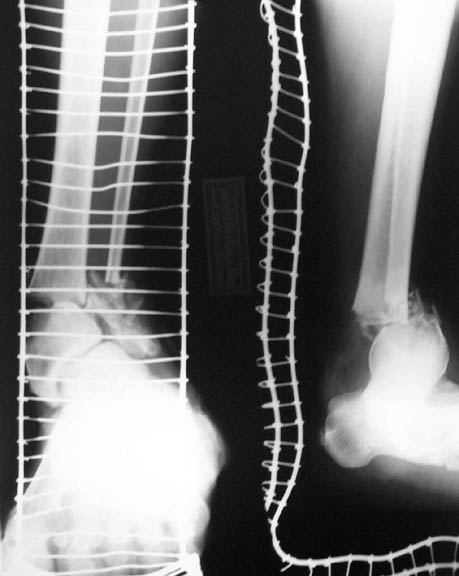

To give the follow up on this patient: A repeat X-ray showed the talus subluxating laterally. A dynamic inversion and eversion strain view pictures showed the lower tibio-fibular syndesmosis opening out. The frame was re-adjusted. Fracture site compressed and valgus corrected. A syndesmotic compression was achieved by adding a washer to the olive and pulling the comminuted lateral malleolus medially. another olive with washer given through talus lateromedially. The equinus that you may see has been corrected. Pictures attached. would welcome critical comments.